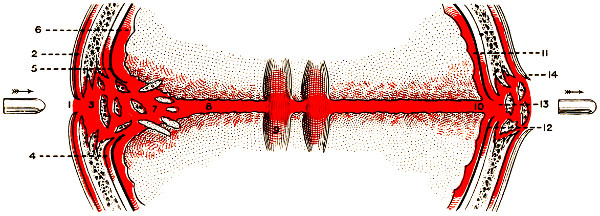

| 51. To illustrate compression of the brain as produced by an extra-dural hæmorrhage from the middle meningeal artery[x] | 141 |

| 52 A and B. The operative treatment of middle meningeal hæmorrhage | 144, 145 |

| 88. Diagrammatic representation of the effects produced on bone and brain by a perforating bullet-wound | 299 |